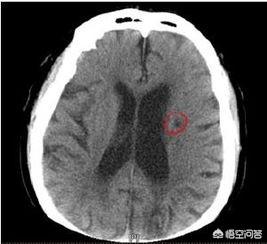

Vingt-quatre à 48 heures après l'apparition de l'infarctus cérébral, la tomodensitométrie du cerveau montre des foyers de faible densité dans les zones correspondantes, avec des limites mal définies, qui peuvent avoir un certain effet d'occupation. L'examen par résonance magnétique cérébrale (IRM) permet de détecter l'infarctus cérébral à un stade plus précoce, ce qui se manifeste par un signal T1 faible dans la zone de la lésion et un signal T2 élevé sur l'image pondérée, et l'IRM permet de détecter des foyers d'infarctus plus petits.

Les lésions d'infarctus cérébral caverneux sont petites et ne sont facilement reconnaissables que par les spécialistes, avec des lésions multiples au milieu de la section cérébrale de l'IRM.